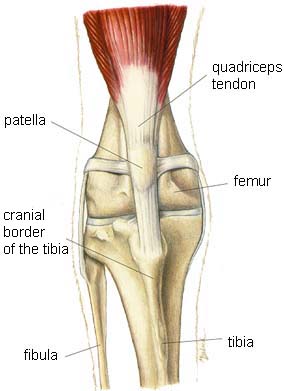

The knee is an amazing, complex joint made up of three bones – the femur, the tibia, and the patella (the kneecap) – held together by tendons, ligaments, and muscle (Figure 1). Where the bones meet, cartilage covers the surface of the bone. The same cartilage provides a smooth surface for the patella to glide, allowing the knee to bend.

Figure 1: Anatomy of the knee (Washington State University (https://hospital.vetmed.wsu.edu/2022/01/04/cat-and-dog-anatomy/))